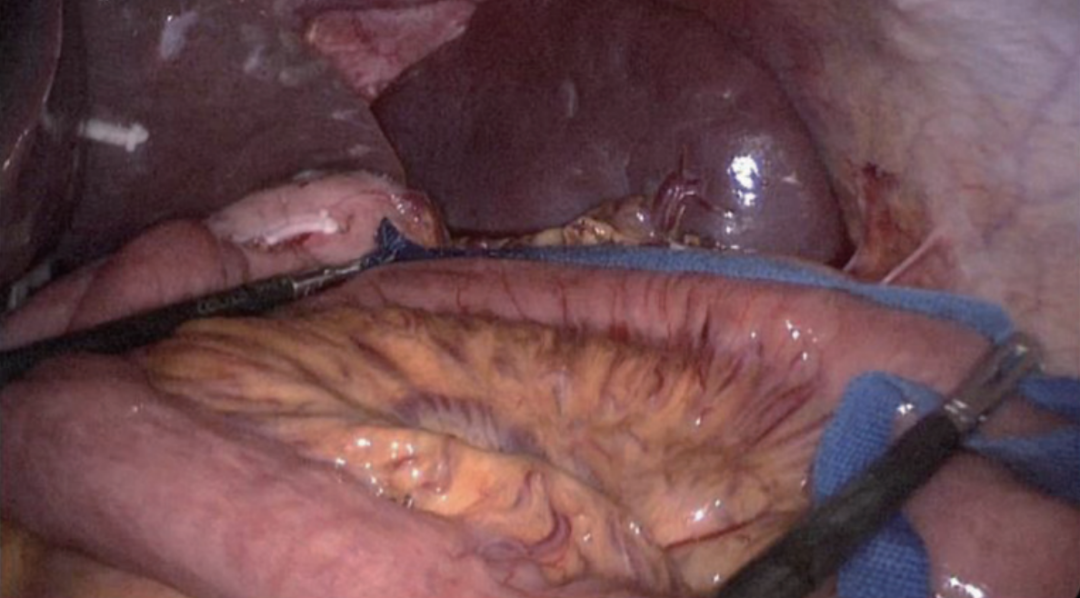

于残胃大弯侧戳孔,戳孔方法分3步。第1步:用超声刀工作头击发刺入胃腔(图27)。第2步:合并超声刀头,击发,于同一孔再次刺入(图28)。第3步:用胃钳或分离钳缓慢撑开戳孔约5 mm(图29)。自屈氏韧带测量空肠40 cm(图30),该处用相同方法戳孔(图31~图33),将直线切割吻合器钉仓臂自远端向近端插入40 cm处空肠戳孔(图34),另一侧插入胃大弯侧戳孔(图35),将残胃与空肠行顺蠕动侧侧吻合。用倒刺线关闭共同开口(共同开口关闭方向应与肠管纵轴垂直)(图36),先全层连续缝合(图36),后浆肌层连续缝合包埋(图37),完成Billroth Ⅱ式吻合(图38~图39)。自胃空肠吻合口分别测量输入袢、输出袢25 cm(图40),分别对系膜缘戳孔,分别插入直线切割吻合器臂,行空肠-空肠侧侧吻合(图41)。用倒刺线关闭共同开口,建议关闭共同开口时,先将输入袢、输出袢肠管向两侧展平,第1针的进针、出针点在相应肠管开口中点,并与肠管长轴平行,完成第1针中间的定位后,再向两侧进行缝合(图42~图43),最后形成以第1针为底部的“U”型缝合线(图44)。

图38 胃-空肠吻合口前面观

图39 胃-空肠吻合口后面观